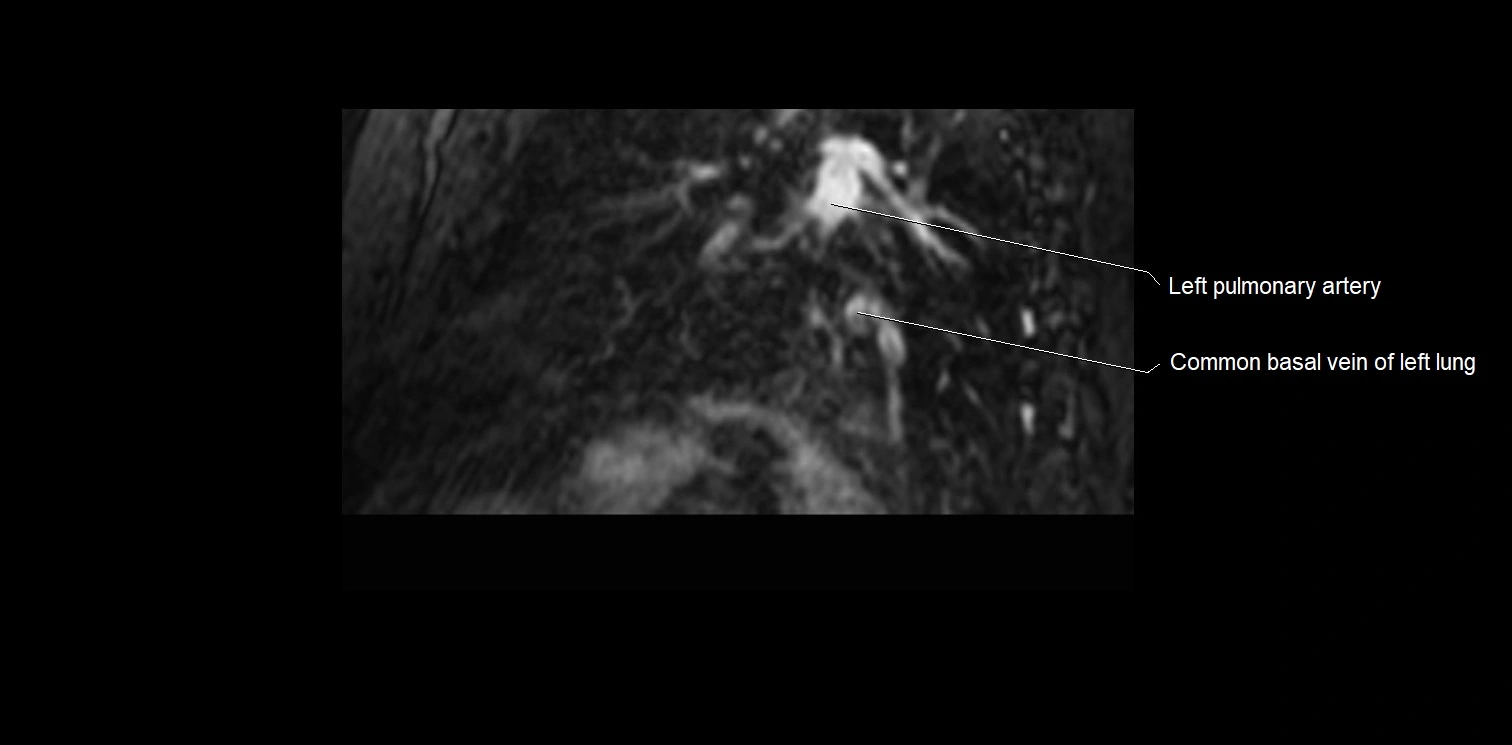

- Left pulmonary artery